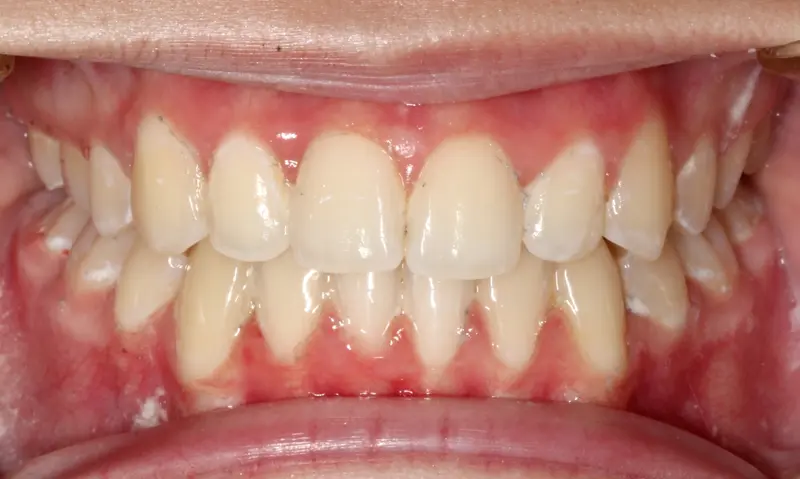

After treatment: The Non-Extraction Arc

After

Before treatment: The Non-Extraction Arc

Before

Severe upper and lower crowding with a narrow maxilla. The smile appeared "hidden" due to the inward angle of the teeth.

We utilized a broad-arch wire sequence combined with passive self-ligating brackets to expand the smile width. By unraveling the crowding without removing teeth, we created a full, consonant smile arc that supports the facial soft tissue.